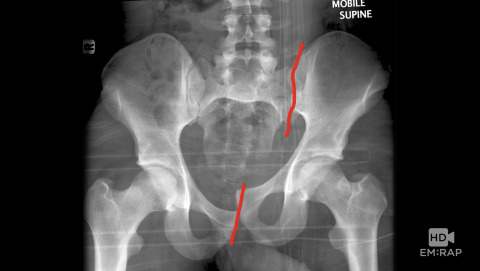

Pelvic Fractures

Dr. Mel Herbert reviews the anatomy of the pelvis, x-ray interpretation, and some of the worst types of pelvic fractures: open book, lateral compression, and vertical shear. Mel also reviews when to use a pelvic binder.